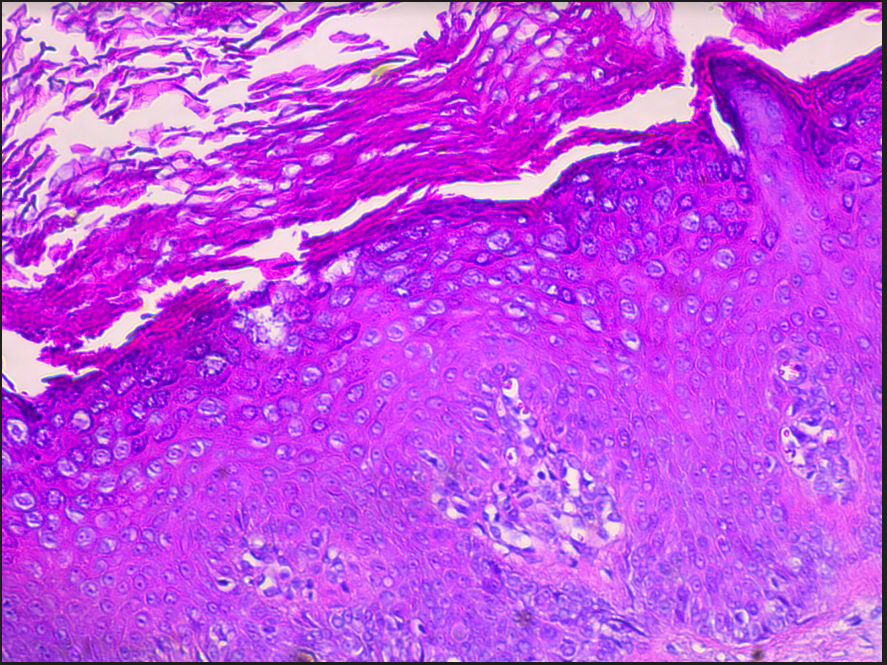

Biopsy of the skin lesions and HP analysis showed orthokeratotic type of hyperkeratosis with a basket weave-like pattern and increased granulous and spinous layers. The cells of these layers were large and the nests of the cellswith prominent perinuclear zone and grayish-blue cytoplasm (vacuolated cells) were present (Figure 2).

Figure 2 Histopathology of the lesion revealed marked hyperkeratosis with basket weave-like pattern; acanthotic epidermis showing keratinocytes with blue-gray cytoplasm, characteristic of EV.